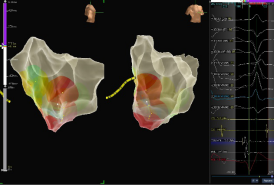

借助超声导管的导引,使用大头在左室内进行激动标测,结合三维标测技术及超声导管的精准定位,定位目标靶点。

图片附件

三维标测结果